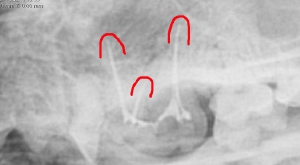

青:根管のアクセスポイント

各々の根管にファイルを挿入し根管長を測定

ポータブルレントゲンによる術中写真

術後の写真 充填( 赤ラインは根先部 )

麻酔なしのレントゲンにおいては2本が重なり一本に見えることもあります。